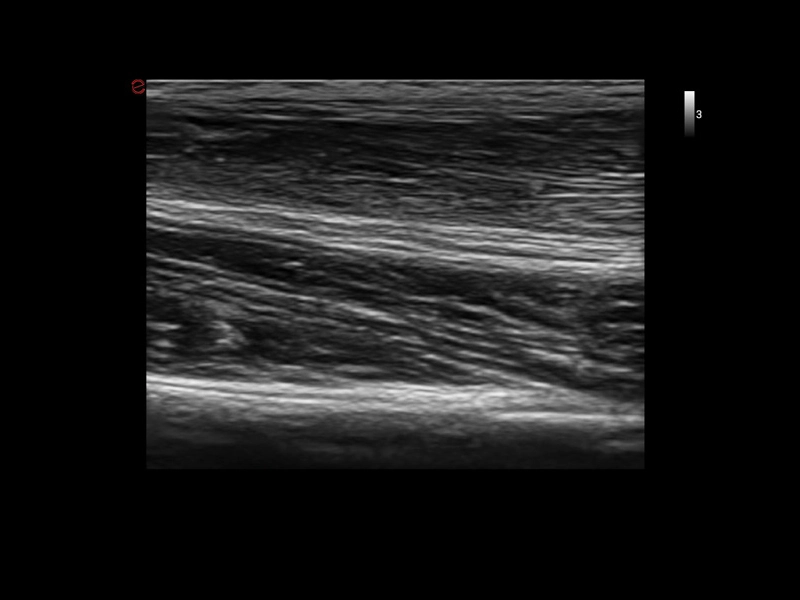

MyLab™E80 - B-Mode - Nerve

MyLab™E80 - B-Mode - Nerve